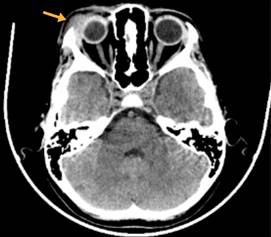

Se realizó una tomografía computarizada (TC) de la región craneal, la cual reveló una lesión lítica en la región frontoorbital, con dimensiones aproximadas de 24 × 19 × 30 mm, que incluía una porción de tejido blando (Figura 2).

Figura 2: Tomografía axial computarizada de cráneo fase simple con ventana para parénquima cerebral, corte axial a nivel de globos oculares en la que se observa aumento de volumen del plano subcutáneo de región supralateral del globo ocular derecho, secundario a presencia de imagen hiperdensa, mal definida, irregular, con ligera extensión intraconal, la cual no condiciona retracción de las estructuras adyacentes o compromiso del componente óseo (flecha amarilla). El globo ocular derecho conserva morfología y densidad, sin datos de infiltración.